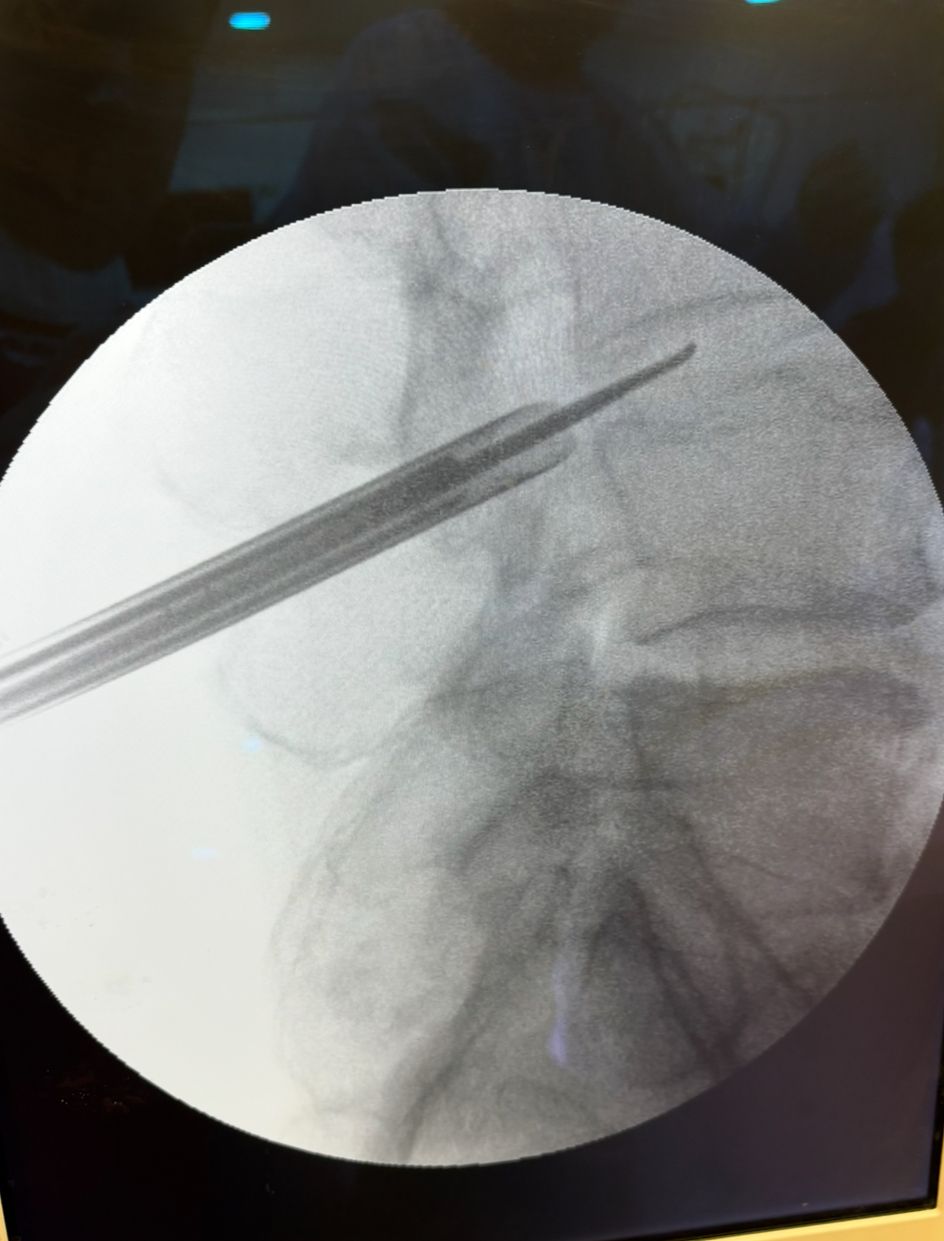

Starszy Asystent w Klinicznym Oddziale Neurochirurgicznym oraz Poradni Neurochirurgii Wojewódzkiego Szpitala Specjalistycznego im. św. Barbary nr 5 w Sosnowcu. Konsultant Kliniki Neurologii Szpitala Klinicznego nr 1 w Zabrzu. Absolwent Wydziału Lekarskiego Śląskiego Uniwersytetu Medycznego w Zabrzu. Staż podyplomowy odbył w latach 2010-2011 w Oddziale Neurochirurgii WSS nr 4 w Bytomiu. W 2018r. złożył egzamin specjalizacyjny po zakończeniu szkolenia w ramach rezydentury w WCM Opole. W 2019 roku uzyskał stopień doktora nauk medycznych. Specjalizuje się w kompleksowym leczeniu schorzeń kręgosłupa (dyskopatia, stenoza kanału kręgowego, kręgozmyk) oraz neuroonkologii. Szczególny zakres działań medycznych to nowoczesne, małoinwazyjne operacje kręgosłupa z wykorzystaniem technik endoskopowych (mikrodiscektomia - implanty rozprężalne), przezskórnych stabilizacji oraz mikrochirurgicznych dekompresji. Wykonuje procedury iniekcyjne; discoGEL, GelSTIX, kriolezje oraz blokady przeciwbólowe kręgosłupa odcinka szyjnego, lędźwiowo-krzyżowego a także stawów krzyżowo-biodrowych, które odgrywają istotną rolę w procesie diagnostyczno-leczniczym wielu zespołów bólowych. Na co dzień przeprowadza operacje w ramach kontraktu z NFZ. Członek Polskiego Towarzystwa Neurochirurgów oraz Polskiego Towarzystwa Chirurgii Kręgosłupa. Uczestnik wielu krajowych i zagranicznych kursów neurochirurgicznych, m.in. w Czechach, Słowacji, Niemczech, Włoszech, Danii, Austrii, Szwajcarii i USA. Autor licznych publikacji naukowych.

Zdjęcia i filmy